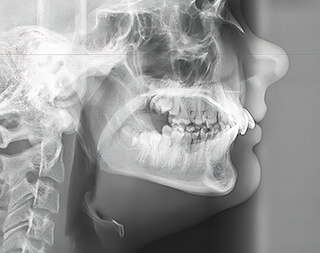

咬み合わせを整えることで、呼吸や全身の姿勢まで変わってきます。咬合適合を行い、顎関節症や口元のバランスの乱れ、肩こりなどの慢性的な症状など改善します。